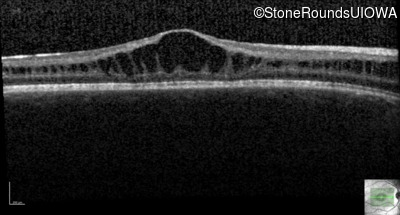

Age at visit: 11 years

This 11 year old male was never correctable to 20/20. He received glasses at age 1 for esotropia. His refraction is +4.25 +2.00 x 105 OD and +2.00 +2.00 x 80 OS.

Age at visit: 13 years

Age at visit: 15 years

Age at visit: 17 years

Age at visit: 18 years